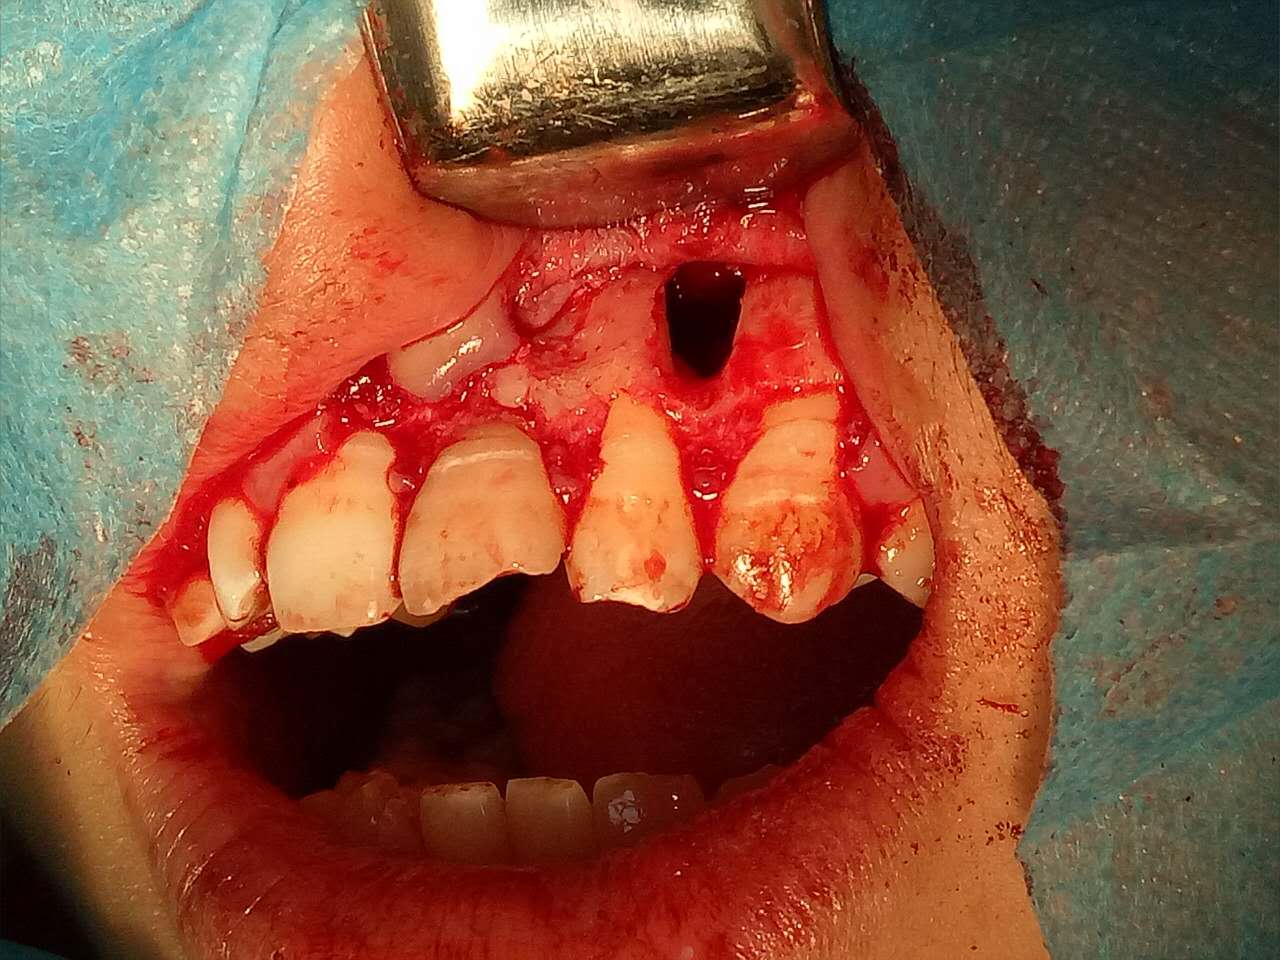

死髓牙2度,沒保留價(jià)值了,外傷造成的外吸收,即使到充也容易出問題。和患者溝通,要求做種植,用了兩個(gè)骨膠原,側(cè)切、尖牙沒事,側(cè)切做了一次根充